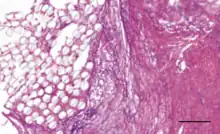

The Ligament Advanced Reinforcement (LARS) is a leading artificial ligament in ACL repair surgery. They are made of polyethylene terephthalate (PET).[3] They consist of an intraosseous and an intra-articular portion. The intraosseous section consists of longitudinal fibers bounded by a knitted transverse structure. This knitted structure can help prevent deformation and abrasion.[5][11] The intra-articular portion is made of longitudinal fibers pretwisted at a 90 degree angle. This section is designed to resist fatigue and promote tissue ingrowth.[5] Leeds Keio ligaments consist of a polyester mesh structure. It seeks to mimic the mechanical properties of the native ACL. The porous nature of the ligament can promote tissue ingrowth which has been shown to improve mechanical properties.[5] The PGA Dacron artificial graft consists of 75% braided biodegradable polyglycolic acid and 25% permanent Dacron thread.[11] The Kennedy LAD artificial ligament is made of polypropylene ribbons. It is designed to promote tissue ingrowth and the progressive transfer of load onto the new ligament.[10]

The primary usage of modern artificial ligaments is in anterior cruciate ligament reconstruction. Many artificial ligaments seek to mimic or exceed the performance of the native ACL.[5] The mechanical performance of an artificial ligament can be characterized by abrasion resistance, withstanding flexural and rotational fatigue,[2] and preventing graft slippage or rupture.[9] Biocompatibility is important to the performance of the artificial ligament in vivo.[3] Biocompatibility is related to new tissue ingrowth,[10] fibroblast migration, osseointegration of bone, reduction of inflammation, preventing scar tissue infiltration, and improving hydrophilicity.[3] Tissue ingrowth and fibroblast migration have been shown to improve the mechanical strength of the artificial ligament,[10] and osseointegration with the surrounding bone can reduce the likelihood of graft slippage.[9] Many artificial ligaments are designed to minimize inflammation and scar tissue infiltration because they can hinder the mechanical strength and can cause graft rupture.[3] Artificial ligament design strives to improve hydrophilicity because hydrophobicity can trigger the host's natural response to foreign bodies.[3]